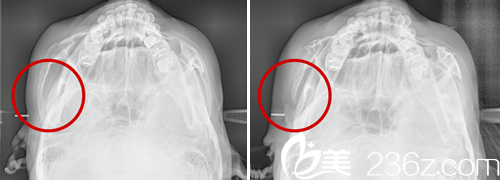

鄭院長會選擇45度顴骨縮小術(shù)進行改善。通過對顴骨部位切開進行旋轉(zhuǎn),從而改變其面部形態(tài),從而達到縮小顴骨的作用,使面部立體而又不失自然。

在術(shù)中,鄭院長會現(xiàn)在前顴骨做L型切口,其次從耳朵上方鬢角位置做一厘米小切口,切開側(cè)顴骨部分并進行回旋固定,從而改善顴骨。